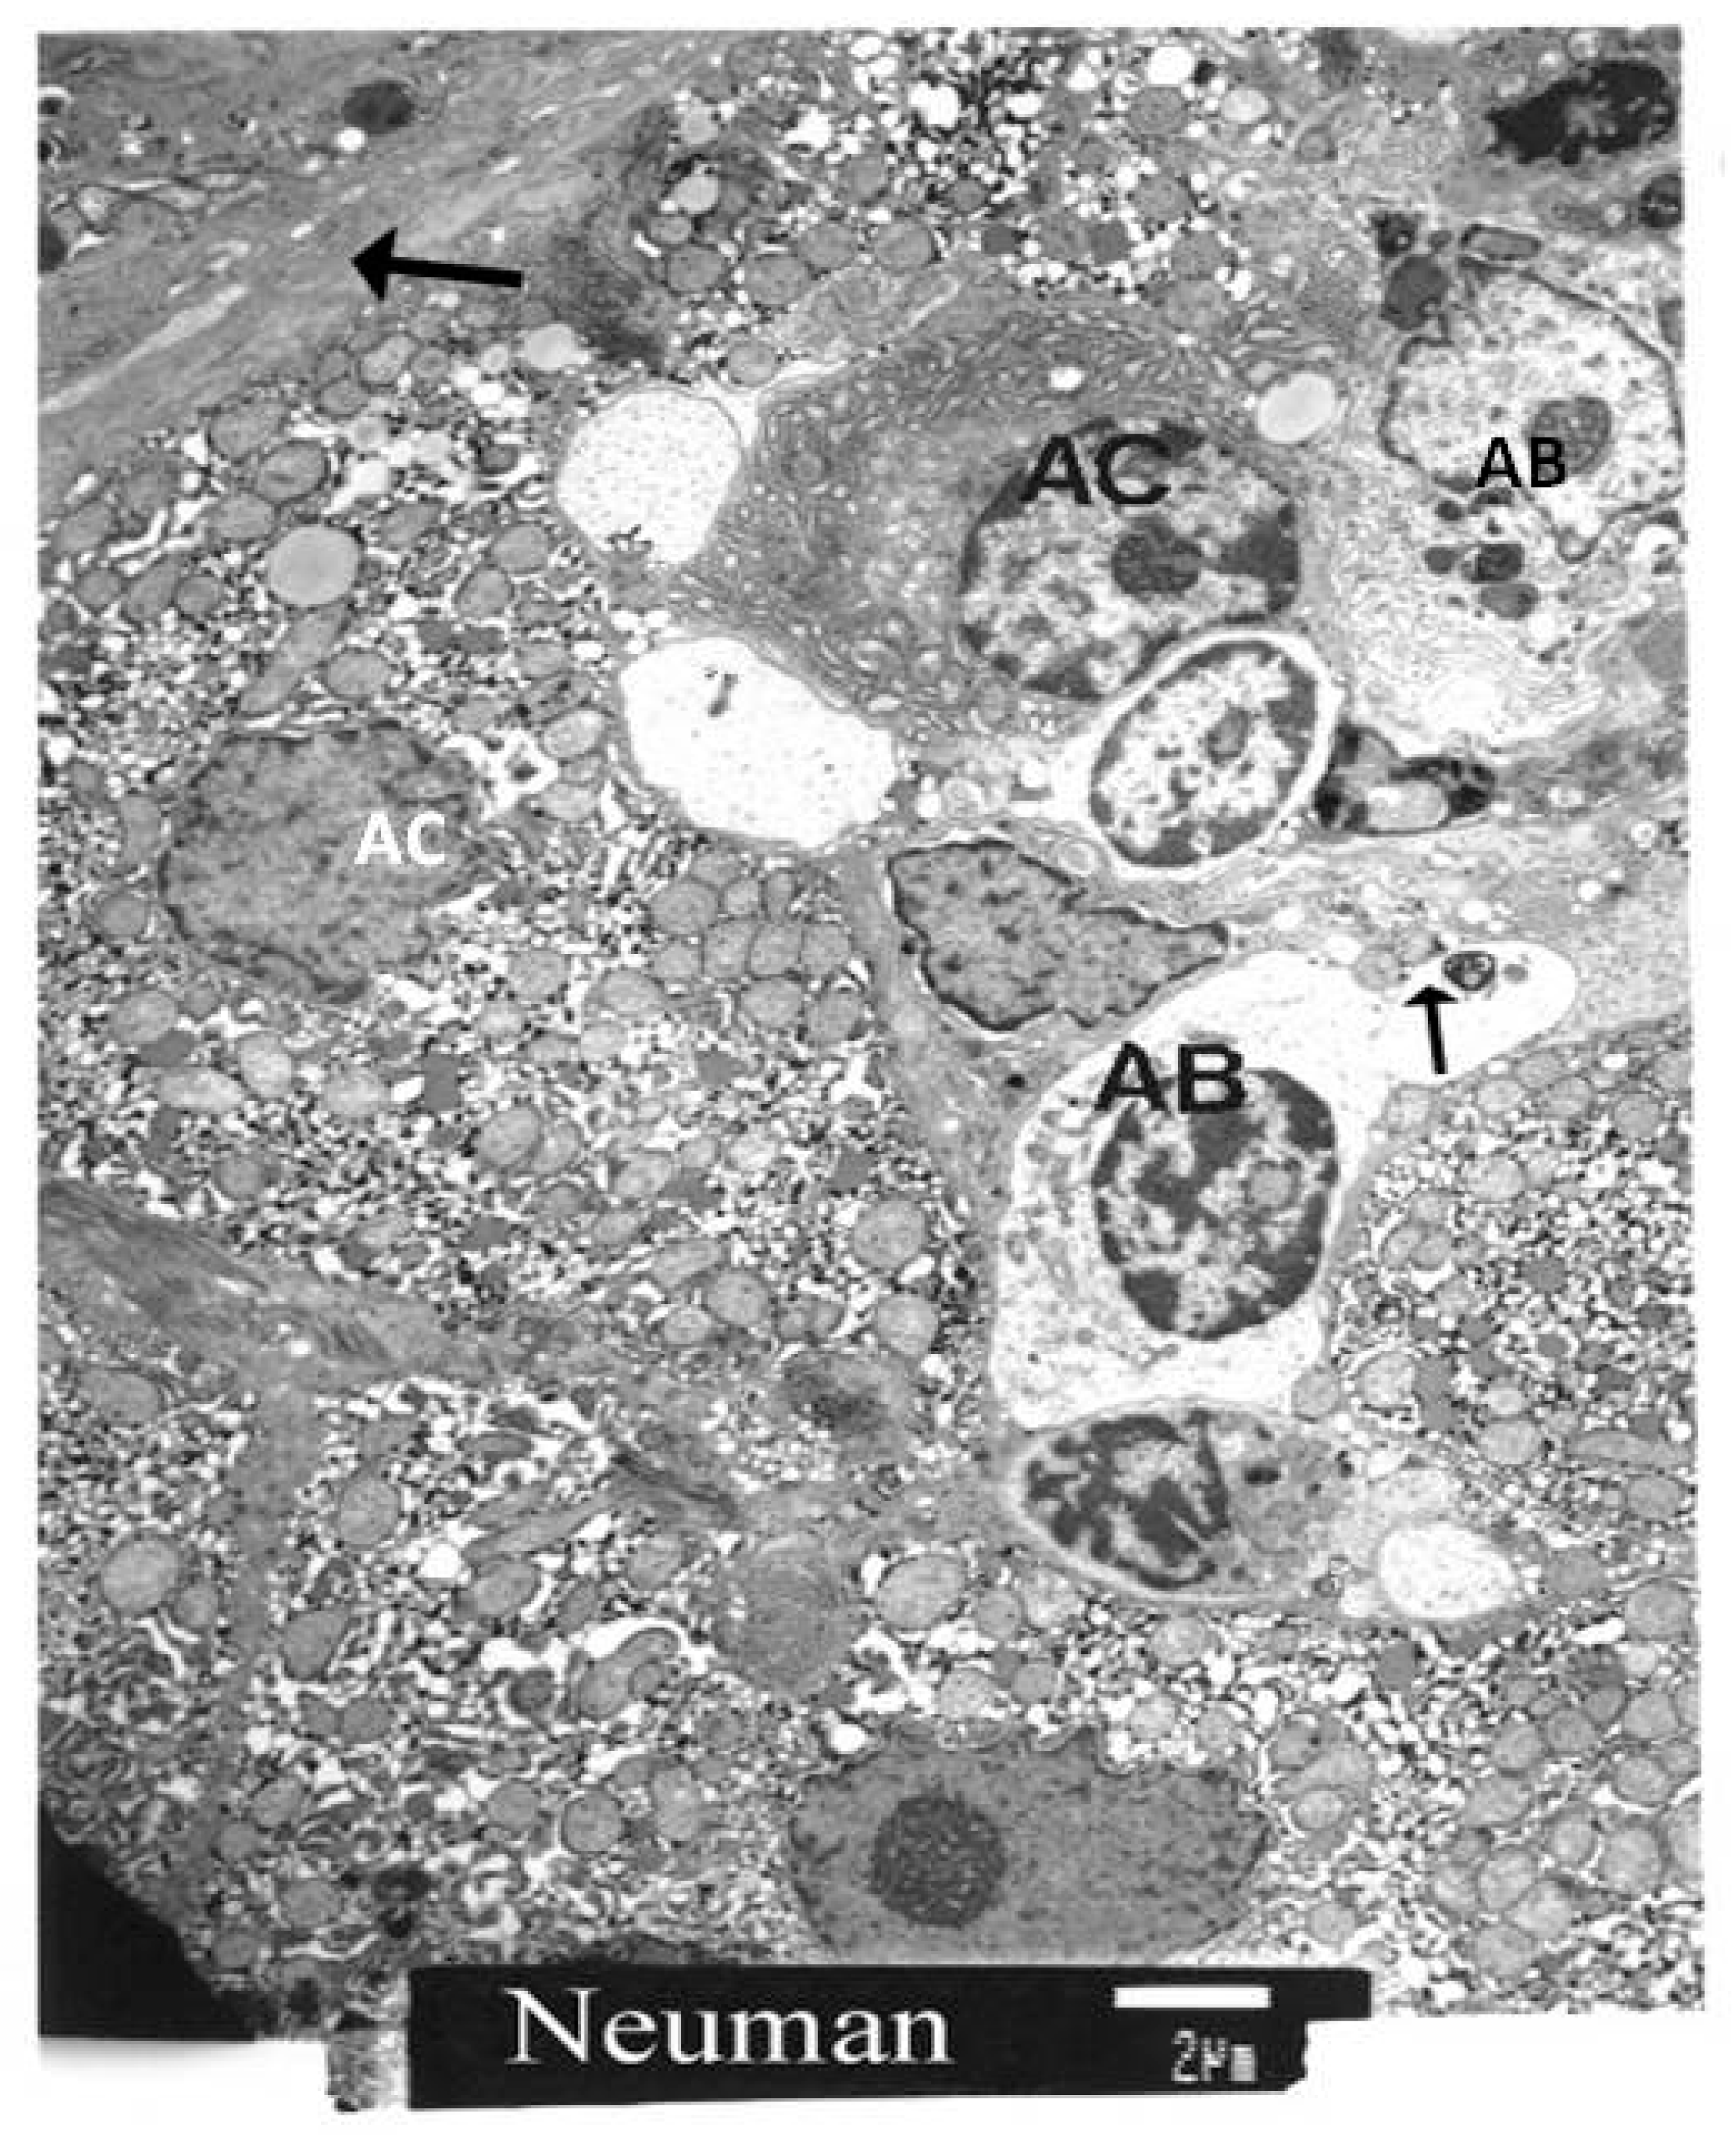

We also focused on the quantification of apoptotic cells (AC) and apoptotic bodies (AB), as well as the quantity of lipid droplets in stellate cells and the amount of collagen present in the perisinusoidal space. The AC counts were made directly from the viewing screen of the electron microscope. The standard unit of comparison was the number of apoptotic cells per randomly selected unit of 100 hepatocytes. Particular attention was paid to the morphological identification of stellate cells.

In the next micrograph (Figure 5), we present the findings from another biopsy. There are apoptotic bodies (AB) and apoptotic cells (AC). One apoptotic cell contains condensed chromatin. Large deposits of collagen are visible in the left upper corner of the micrograph.

Figure 5.

TEM of a biopsy. A shrunken apoptotic cell with a shrunken chromogen nucleus is at the bottom of the micrograph. Other apoptotic cells are scattered in the micrograph. Apoptotic bodies (AB) can be observed. The arrow points to fragments of cellular debris.